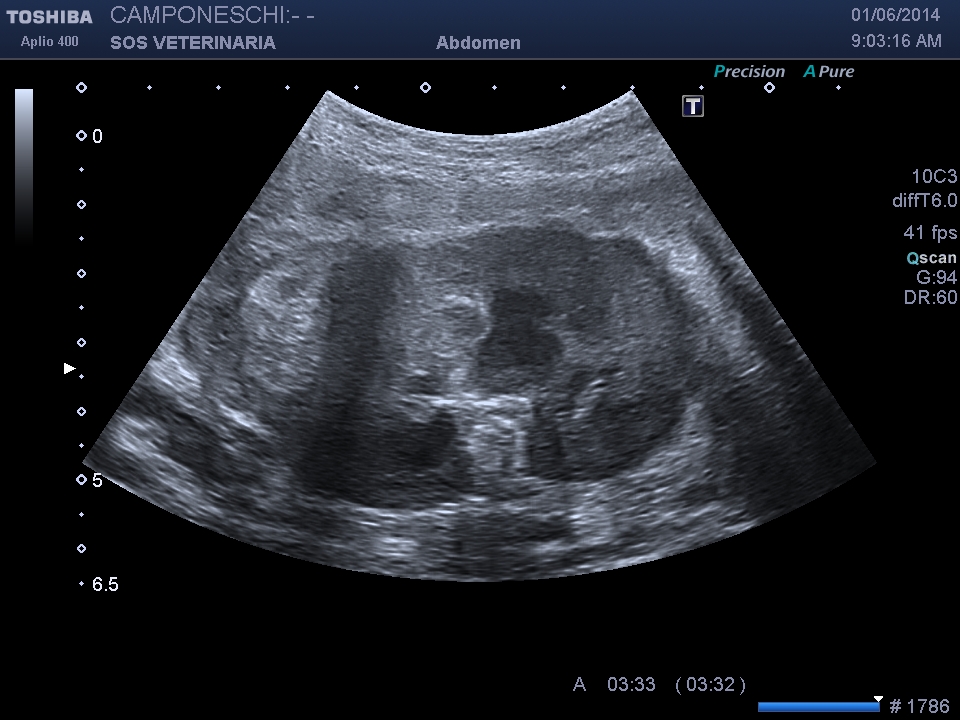

infarcimento emorragico acuto